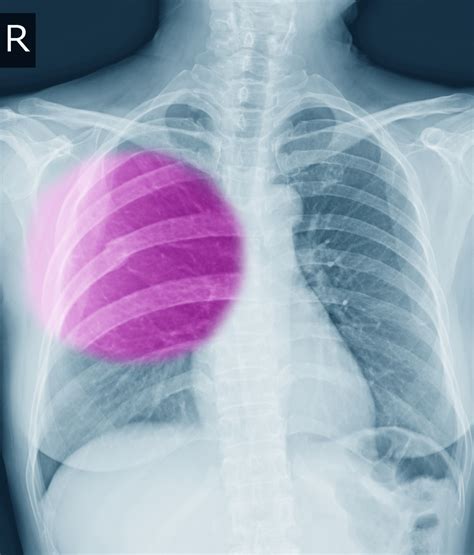

Rib fractures